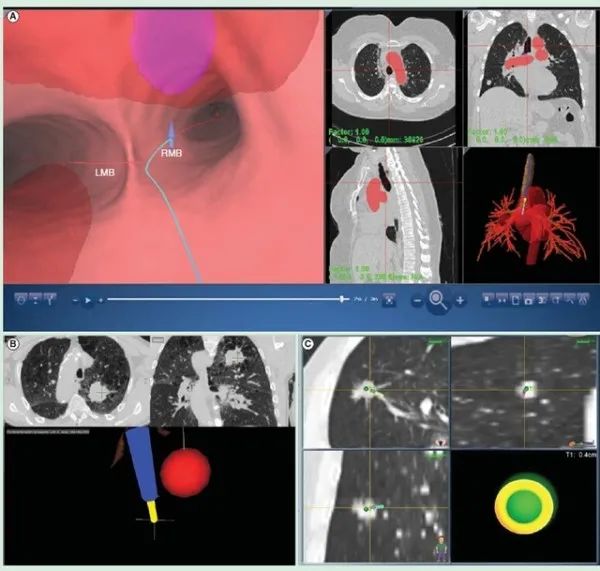

支气管镜是一种带有光源和镜头的软镜,一般从鼻腔置入,通过咽喉、会厌、声门进到气管及细支气管,用来进行肺和气管、支气管病变的诊断和治疗一项检查。